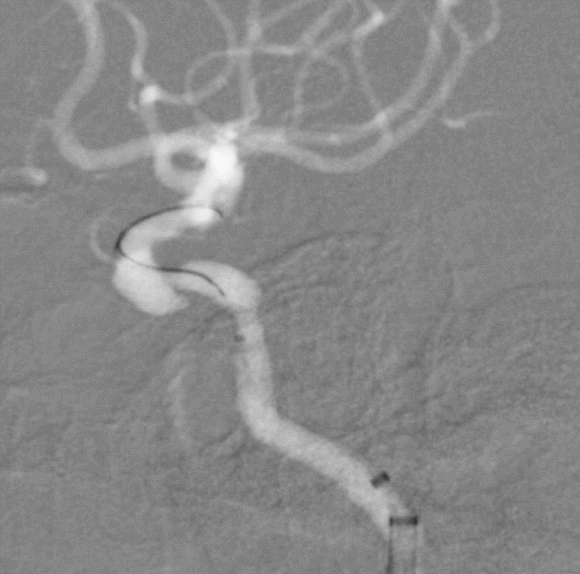

术后3月复查,瘤体未见显影,载瘤动脉通畅

同期4mm×20mm Streamline 进一步处理右侧动脉瘤